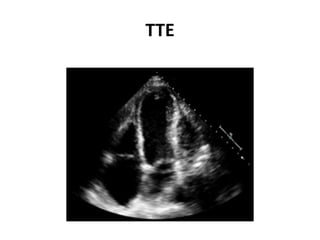

clopidogrel, and discharged.

• Repeat TTE was performed

TTE

Echo showed pericardial fluid collection, measuring

3.2 cm and causing indentation of the left